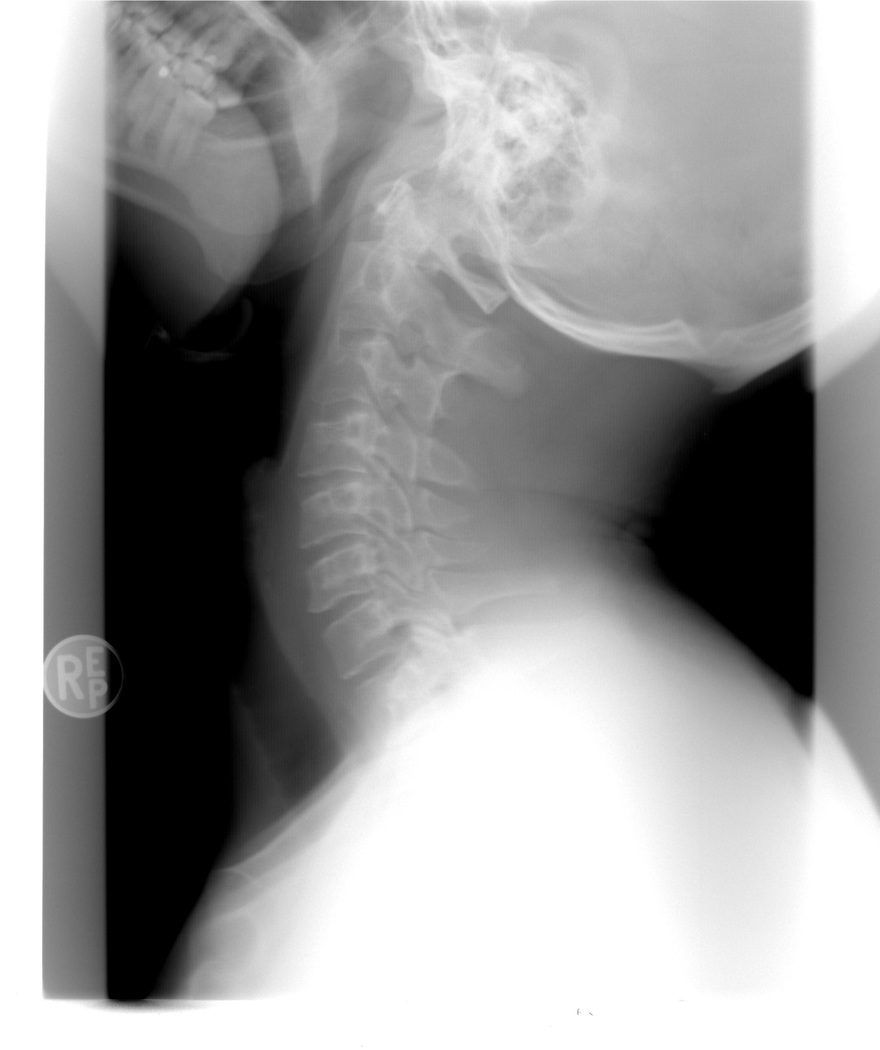

Whiplash letsel heeft ernstige gevolgen. Behandelaars nemen de klachten niet altijd serieus. Wij helpen u uw letselschade te claimen.| Letselschadespecialist.nl